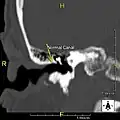

Normal ear canal

Exostosis in ear canal